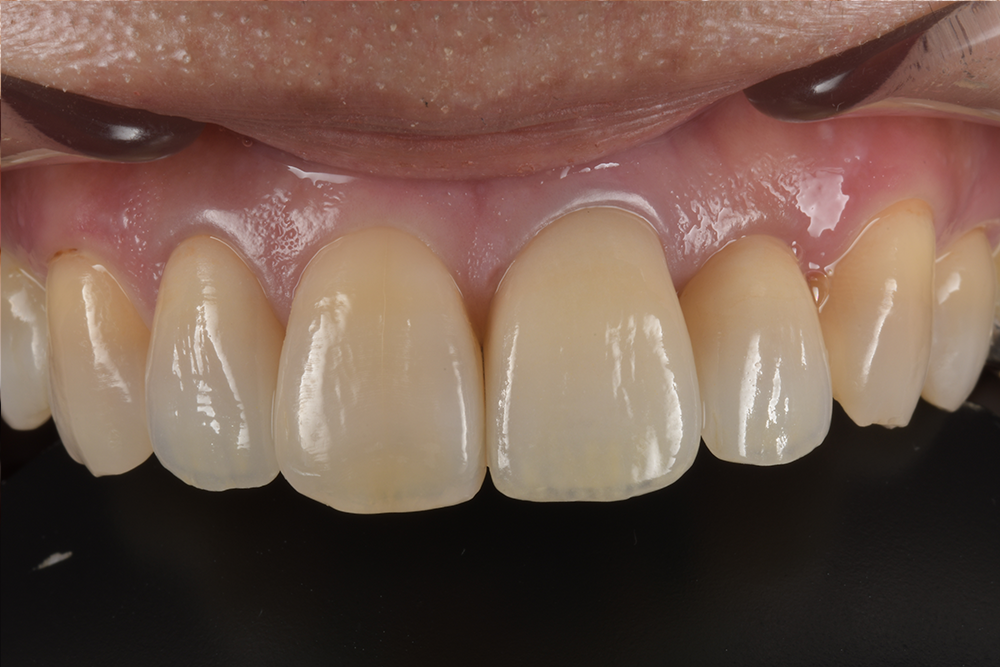

前歯が欠けた(60代)セラミック修復・ホワイトニング

年齢 67歳 性別 女性 初診日 2022年7月 主訴 審美障害 治療内容 セラミック修復・ホワイトニング 治療期間 4ヶ月 治療費用 約50万円 治療経過 前歯が欠けたとのことで来院された。 元々装着されていたラミネートベニアの破折であった。 ラミネートベニアのや…